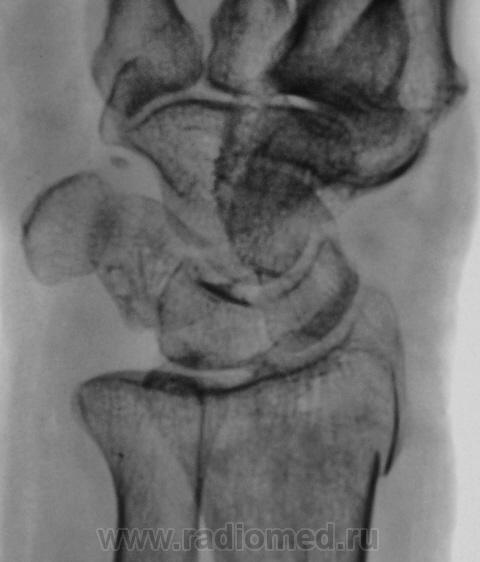

Травма.   Пациент направлен на рентгенографию лучезапястного сустава.